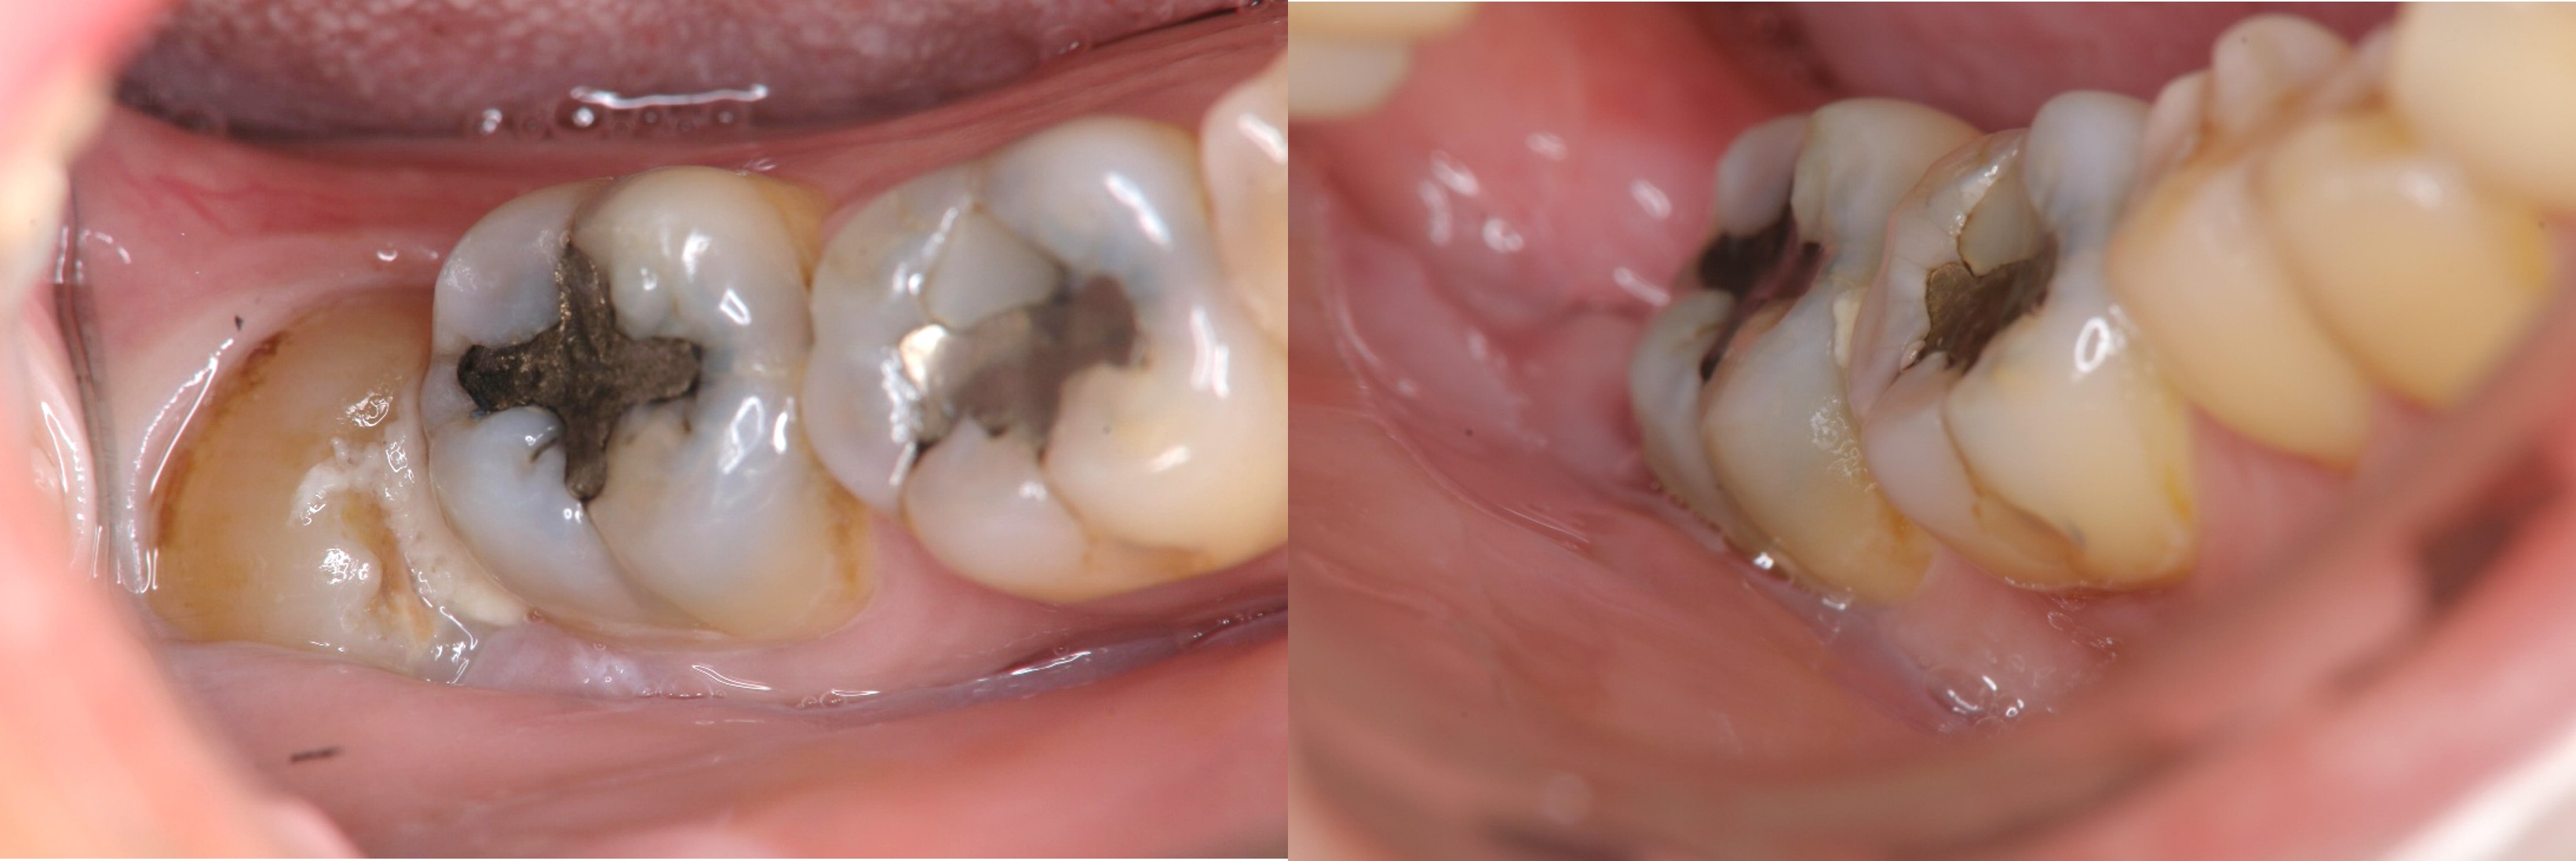

治療前,右下阻生齒造成牙周腫脹

術前、術後比較